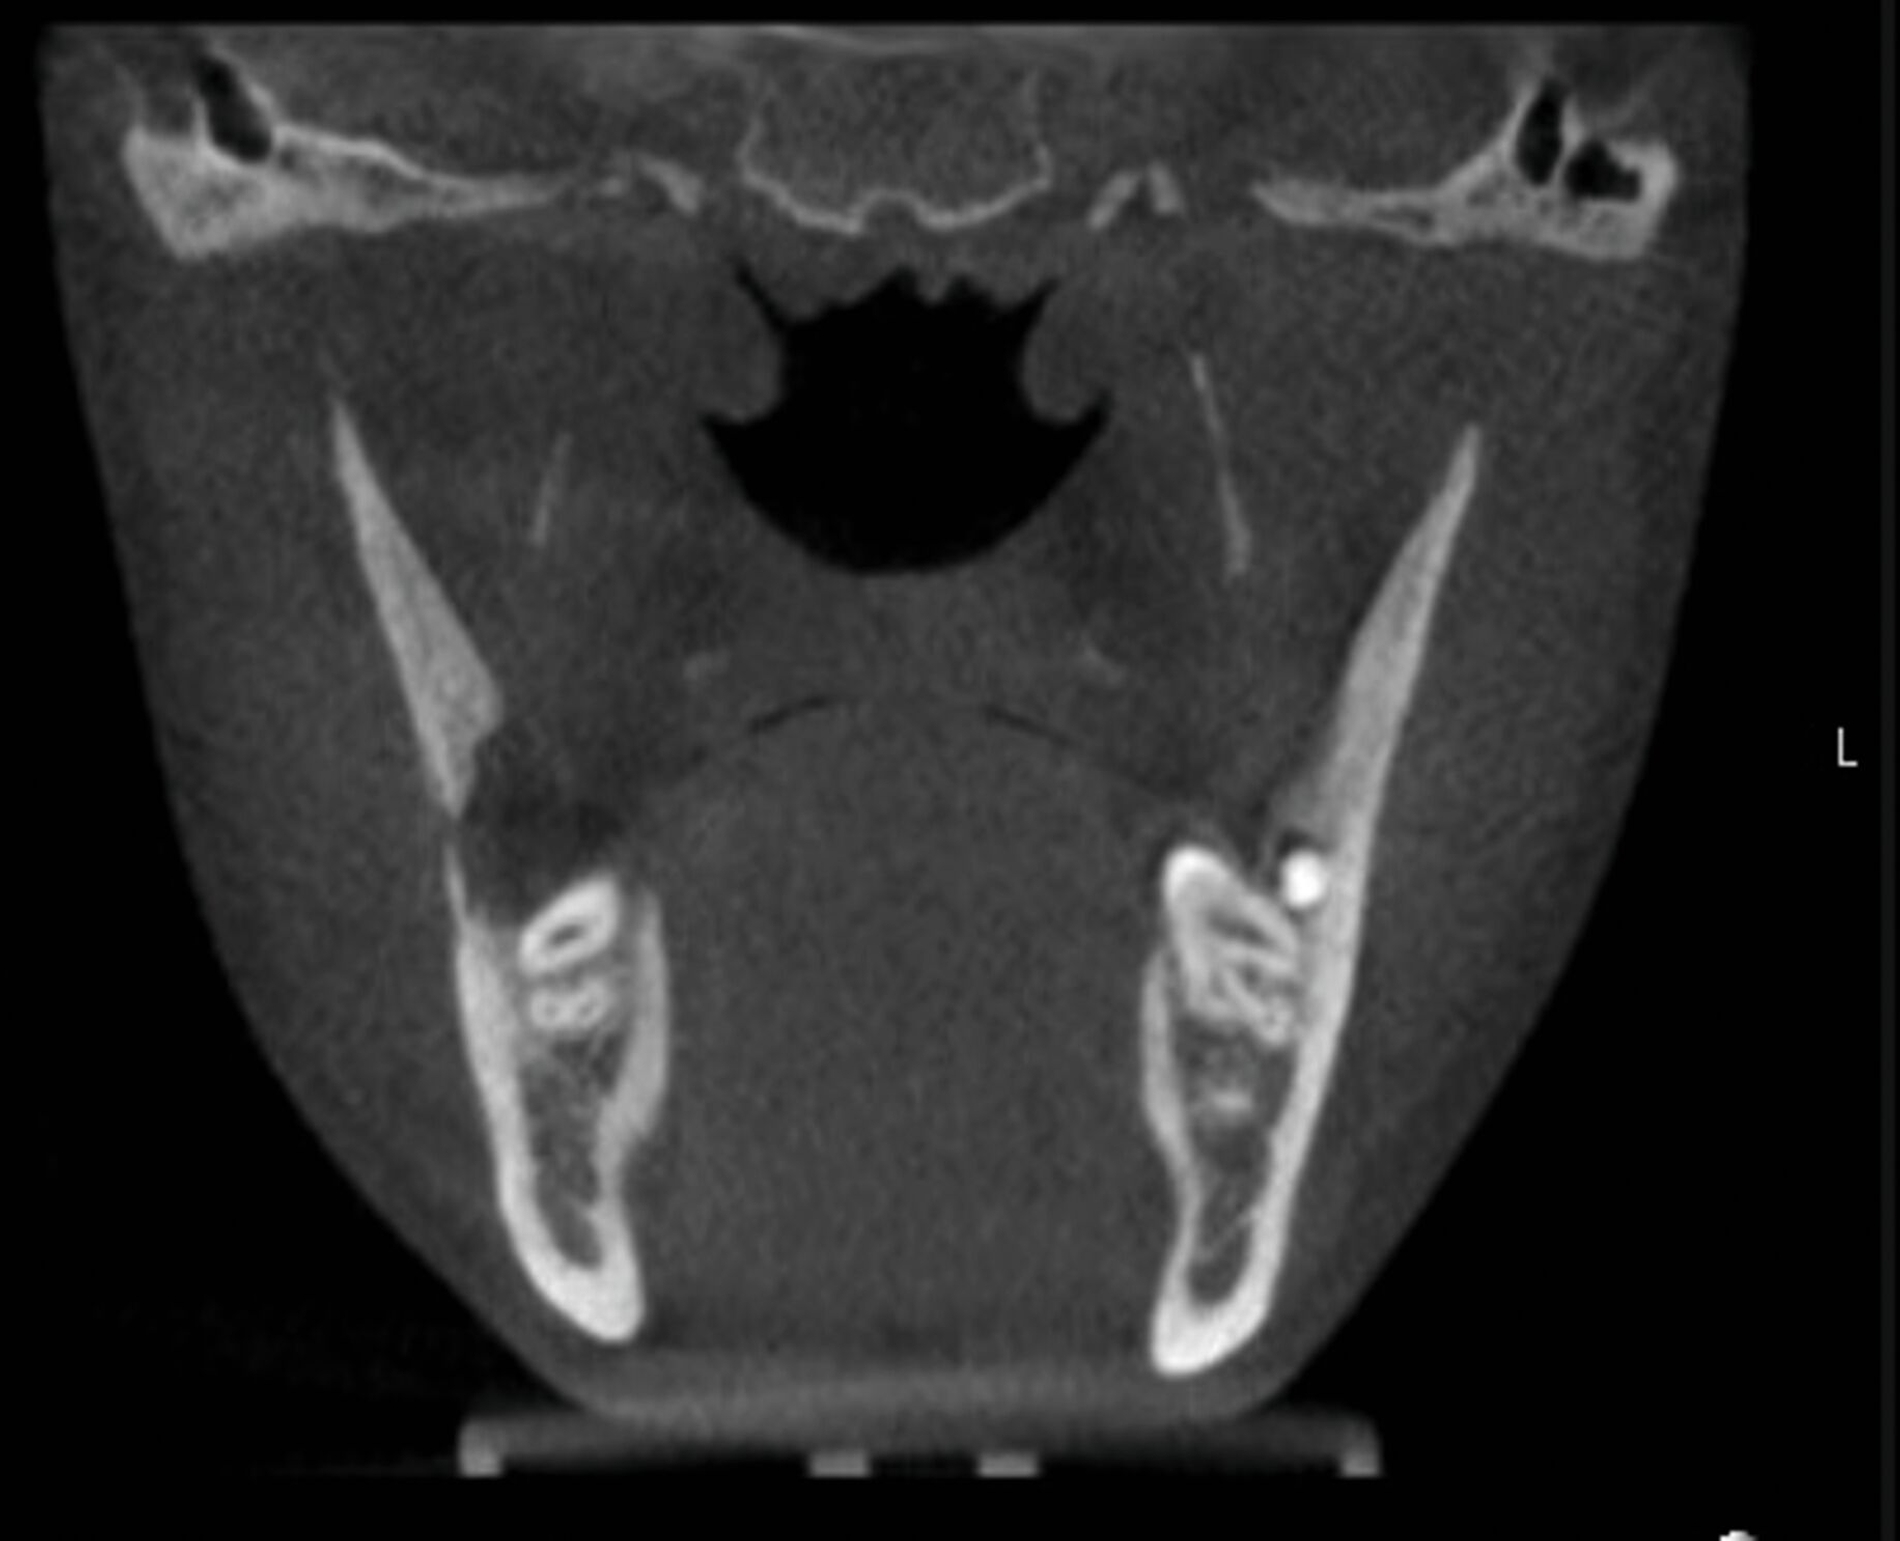

Dieser Patient stellte sich nun mit Schmerzen und Druckdolenz im Kieferwinkel rechts vor. Der enorale Befund zeigte weder eine Fehlokklusion noch ein Os liberum, die faziale Sensomotorik war seitengleich intakt. Die allgemeine Anamnese förderte jedoch eine Osteogenesis imperfecta Typ I zutage („Glasknochenkrankheit“). Das ad domo angefertigte DVT ergab den Befund einer Fraktur an der Linea obliqua rechts (Abbildung 2).